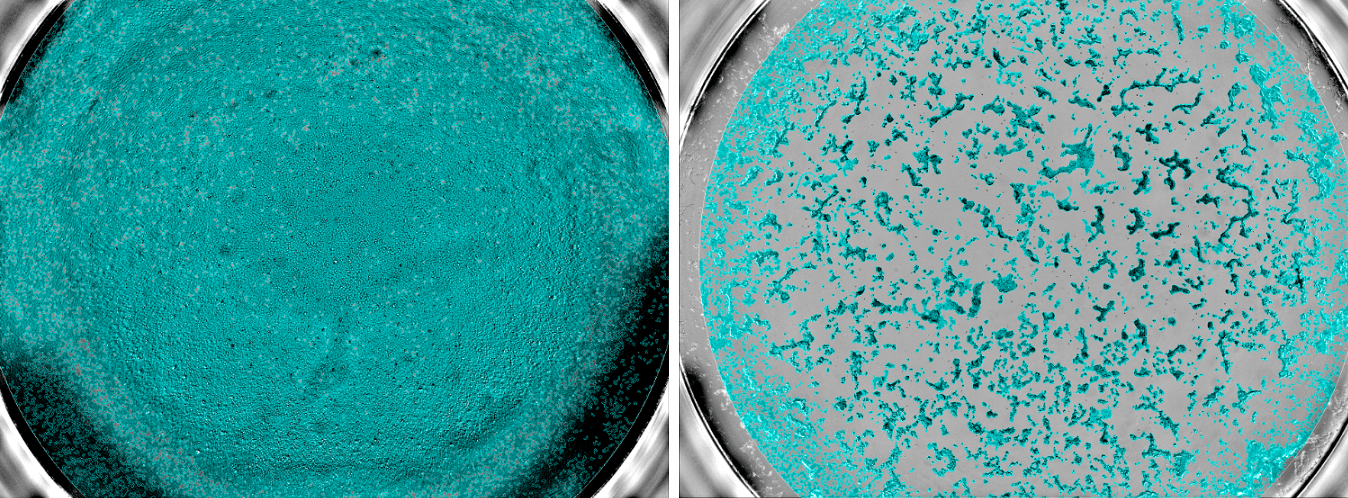

Echantillons sanguins dans la cohorte Constances et tests sérologiques de l’infection au virus SARS-Cov-2. A gauche : des cellules non infectées par le virus SARS-CoV-2, preuve que l’échantillon de sang contenait des anticorps neutralisants capable d’empêcher le virus d’entrer dans les cellules. A droite : de nombreuses cellules ont été détruites, preuve de l’absence d’anticorps neutralisants contre le virus. ©Unité des Virus Émergents (Inserm – Aix Marseille Université – IRD)

Le test de neutralisation avec le virus SARS-CoV-2 infectieux est plus fastidieux à mettre en œuvre car il nécessite une manipulation en laboratoire P3. Il utilise une dose fixe de virus qui détruit 100 % des cellules. Après mélange avec différentes dilutions de sérum, on observe si la présence d’anticorps anti-SARS-CoV-2 permet de neutraliser le virus et donc d’inhiber la multiplication virale et par conséquent d’empêcher la destruction des cellules.